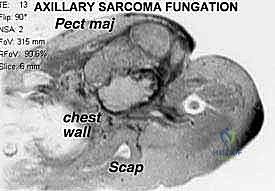

Lumbar degenerative scoliosis may be characterized by loss of lordosis and intervertebral disc height as well as listhesis in the anteroposterior, lateral, or rotary direction (FIG 1A,B).

Long curves, typically the result of a preexisting spinal deformity, may involve the entire thoracolumbar spine and may be associated with a significant rotational component (FIG 1C,D).

FIG 1 • A,B. Degenerative lumbar scoliosis, with mild degree of deformity, in PA (A) and lateral (B) radiographs. Small lateral, rotary, and anterolistheses are seen, with significant loss of disc height, osteophyte formation, and subchondral sclerosis. The coronal deformity is limited to the lumbar region. C,D. A longer scoliosis, and of more significant degree, involving the lumbar and thoracic regions, and associated with rotational deformity, is shown in PA (C) and lateral (D) radiographs.*